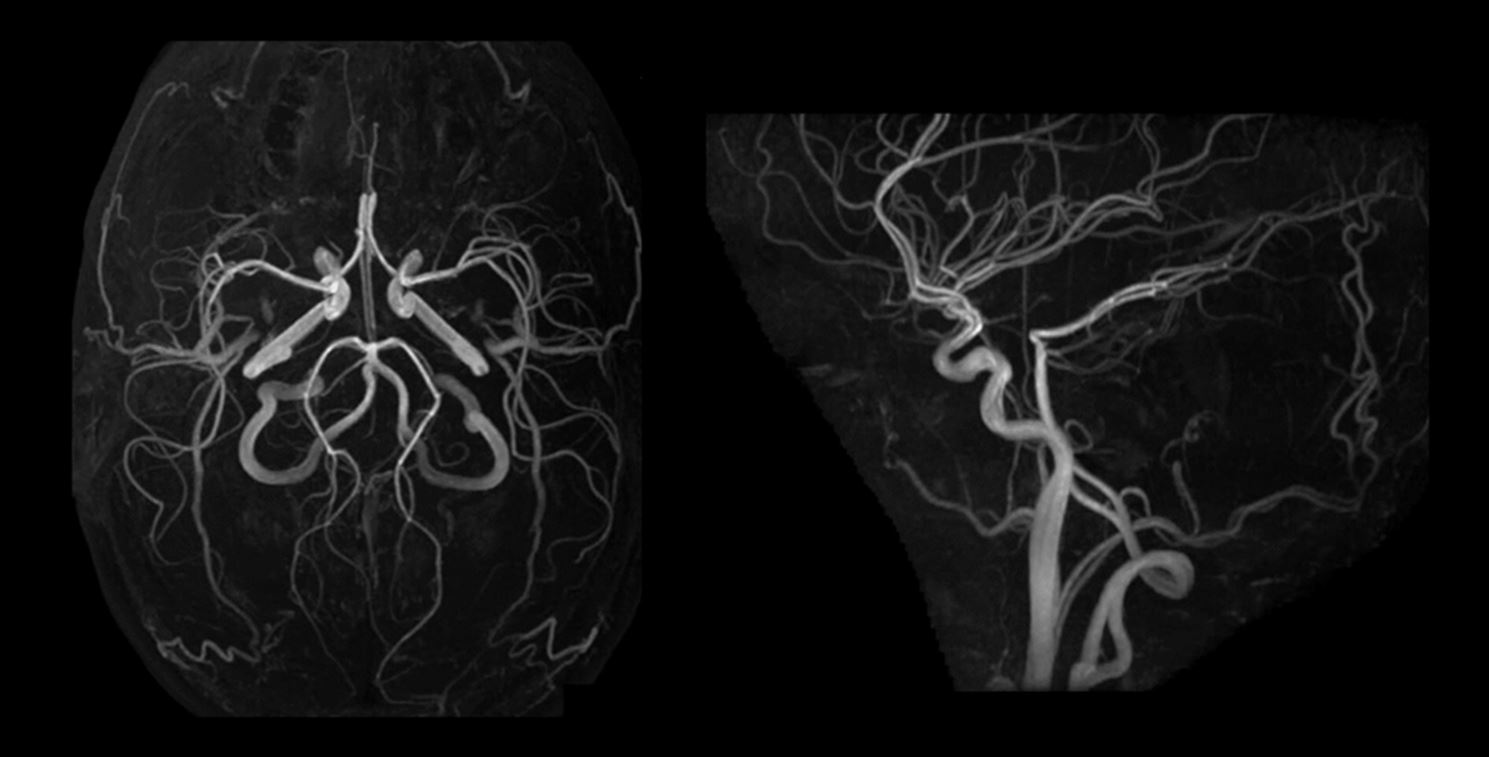

Μετά την απόκτηση των εικόνων της MRA εγκεφάλου, απαιτείται μετεπεξεργασία των δεδομένων, η οποία επιτρέπει την παραγωγή  εικόνων που μοιάζουν με αυτές τις ψηφιακής αγγειογραφίας, με το μέγιστο δυνατό σήμα από τα αγγεία και το ελάχιστο δυνατό σήμα από τους πέριξ στατικούς ιστούς (εικόνα κάτω). Πιο συγκεκριμένα, πρέπει να γίνεται χρήση των τεχνικών maximum intensity projection (MIP), volume rendering (VR), shaded surface display (SSD), καθώς και πολυεπίπεδες ανασυνθέσεις με σκοπό την βέλτιστη αξιολόγηση των ενδοκρανιακών αρτηριών.